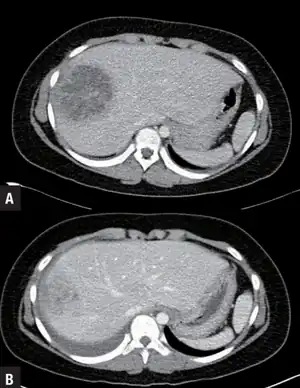

| A large pyogenic liver abscess presumed to be the result of appendicitis | |

a)Day 1 showing pyogenic liver abscess b)hospital day 21 showing improved pyogenic liver abscess, after intravenous antibiotic